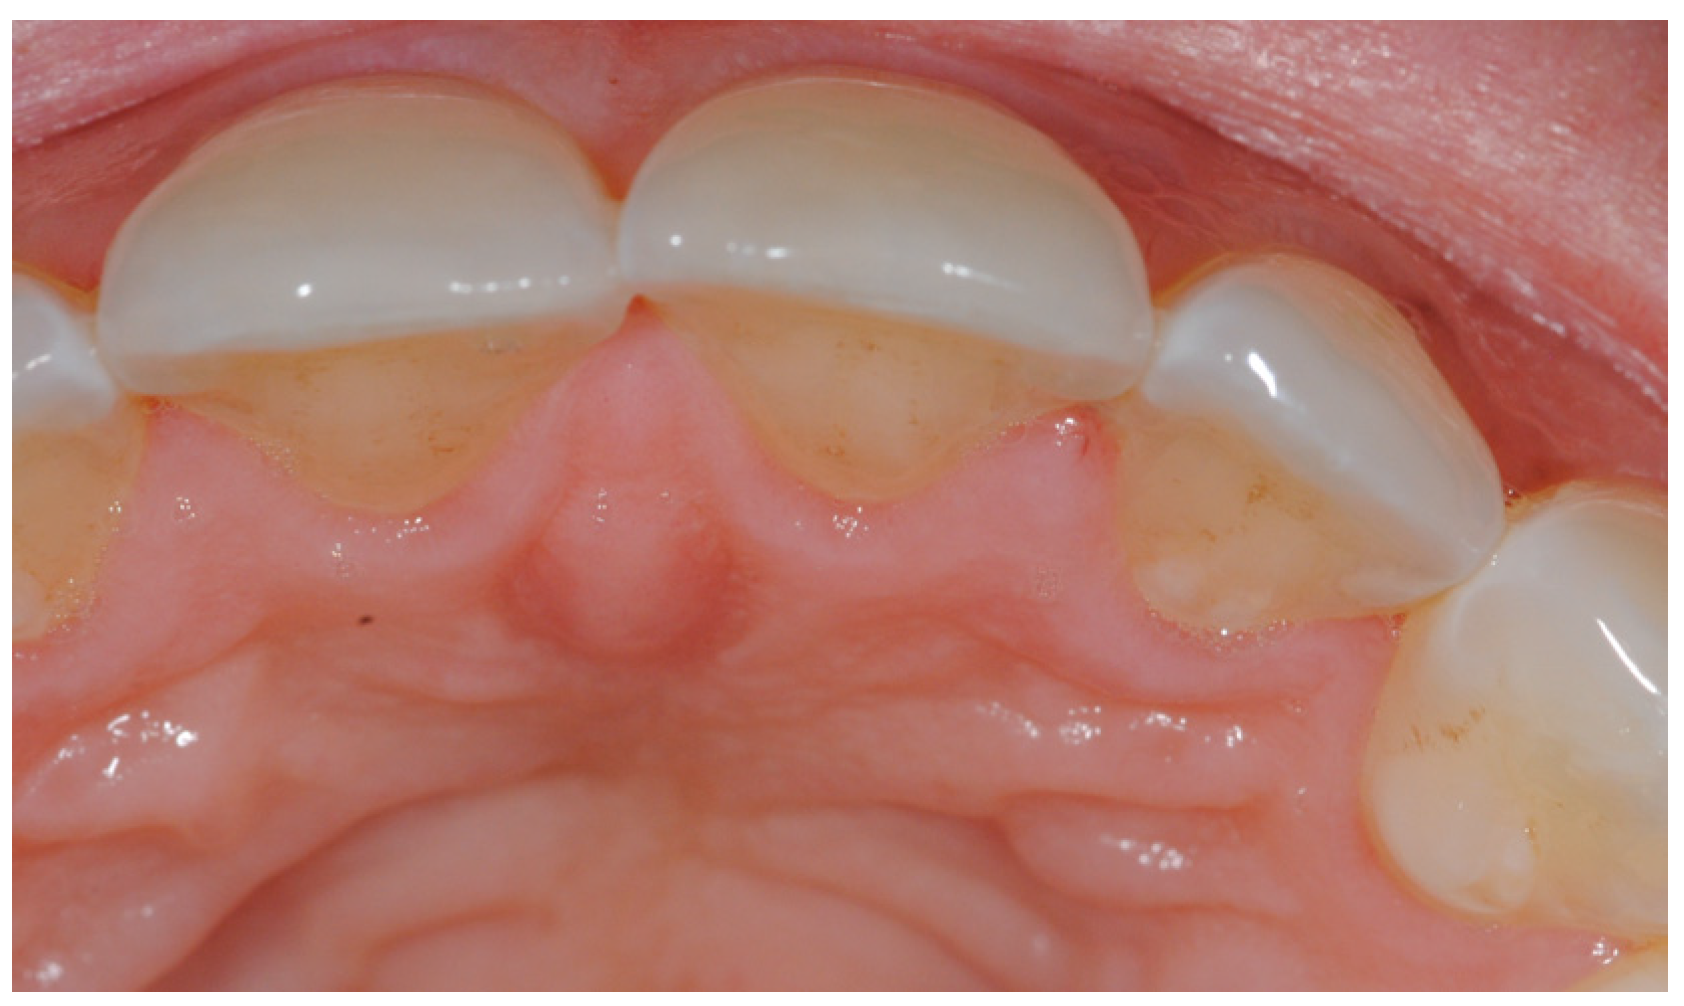

2. Case Presentation